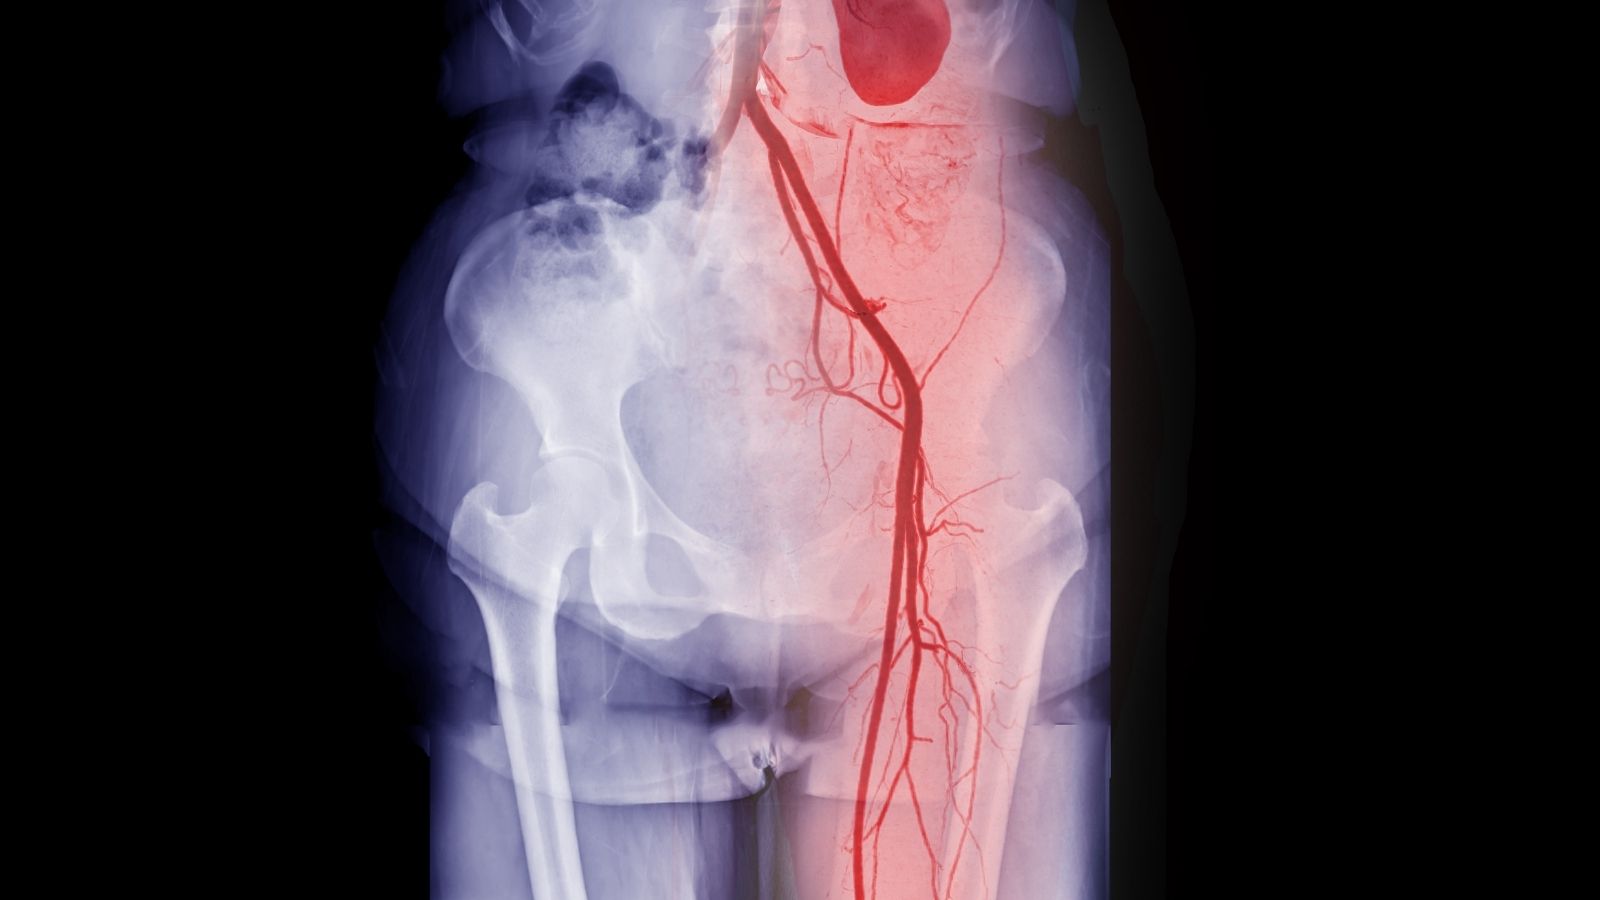

Marfan sendromunun en ciddi ve yaşamı tehdit eden komplikasyonları kalp ve damar sisteminde ortaya çıkar. Bu yüzden sendromun takibi ve tedavisi büyük ölçüde bir kardiyolog ve kalp cerrahı tarafından yönetilir. Sorunun merkezinde, vücudun en büyük atardamarı olan ve kalpten çıkan aort damarı yer alır. Aort, kalbin her atışında yüksek basınçlı kanı tüm vücuda dağıtan ana boru hattıdır. Bu muazzam basınca dayanabilmesi için duvarlarının çok sağlam ve esnek olması gerekir. İşte Marfan sendromunda, bağ dokusundaki zayıflık nedeniyle aort duvarı bu direncini kaybeder. Zamanla, içindeki kan basıncının etkisiyle tıpkı bir balon gibi yavaş yavaş genişlemeye başlar. Bu duruma “aort anevrizması” denir.

Anevrizmanın kendisi başlangıçta bir belirti vermeyebilir, ancak asıl tehlike sessizce büyümesidir. Belirli bir çapa ulaştığında, bu zayıflamış damar duvarı ya tamamen yırtılabilir (rüptür) ya da iç katmanlarından yırtılarak kanın damar duvarları arasına sızmasına (aort diseksiyonu) neden olabilir. Her iki durum da acil cerrahi müdahale gerektiren, ölümcül olabilen durumlardır. Bu nedenle Marfan sendromu takibinin temel amacı, bu “saatli bomba”yı patlamadan önce tespit etmek ve önleyici ameliyatla etkisiz hale getirmektir.

İlaç tedavisi ve yaşam tarzı değişikliklerine rağmen aort damarındaki genişleme devam edebilir. Aort çapı, yırtılma riskinin kabul edilemez derecede yükseldiği kritik bir eşiğe ulaştığında, “önleyici” yani profilaktik ameliyat gündeme gelir. Buradaki felsefe, felaketin gerçekleşmesini beklemek değil ondan önce davranarak riski ortadan kaldırmaktır.

Ameliyat kararı için en önemli kriter aort kökünün çapıdır. Genel olarak kabul edilen eşikler şunlardır:

- Risk faktörü olmayan hastalarda aort çapı 5.0 cm’ye ulaştığında

- Ailede aort diseksiyonu öyküsü, hızlı büyüme, ciddi kapak yetmezliği gibi ek risk faktörleri varsa 4.5 cm’de